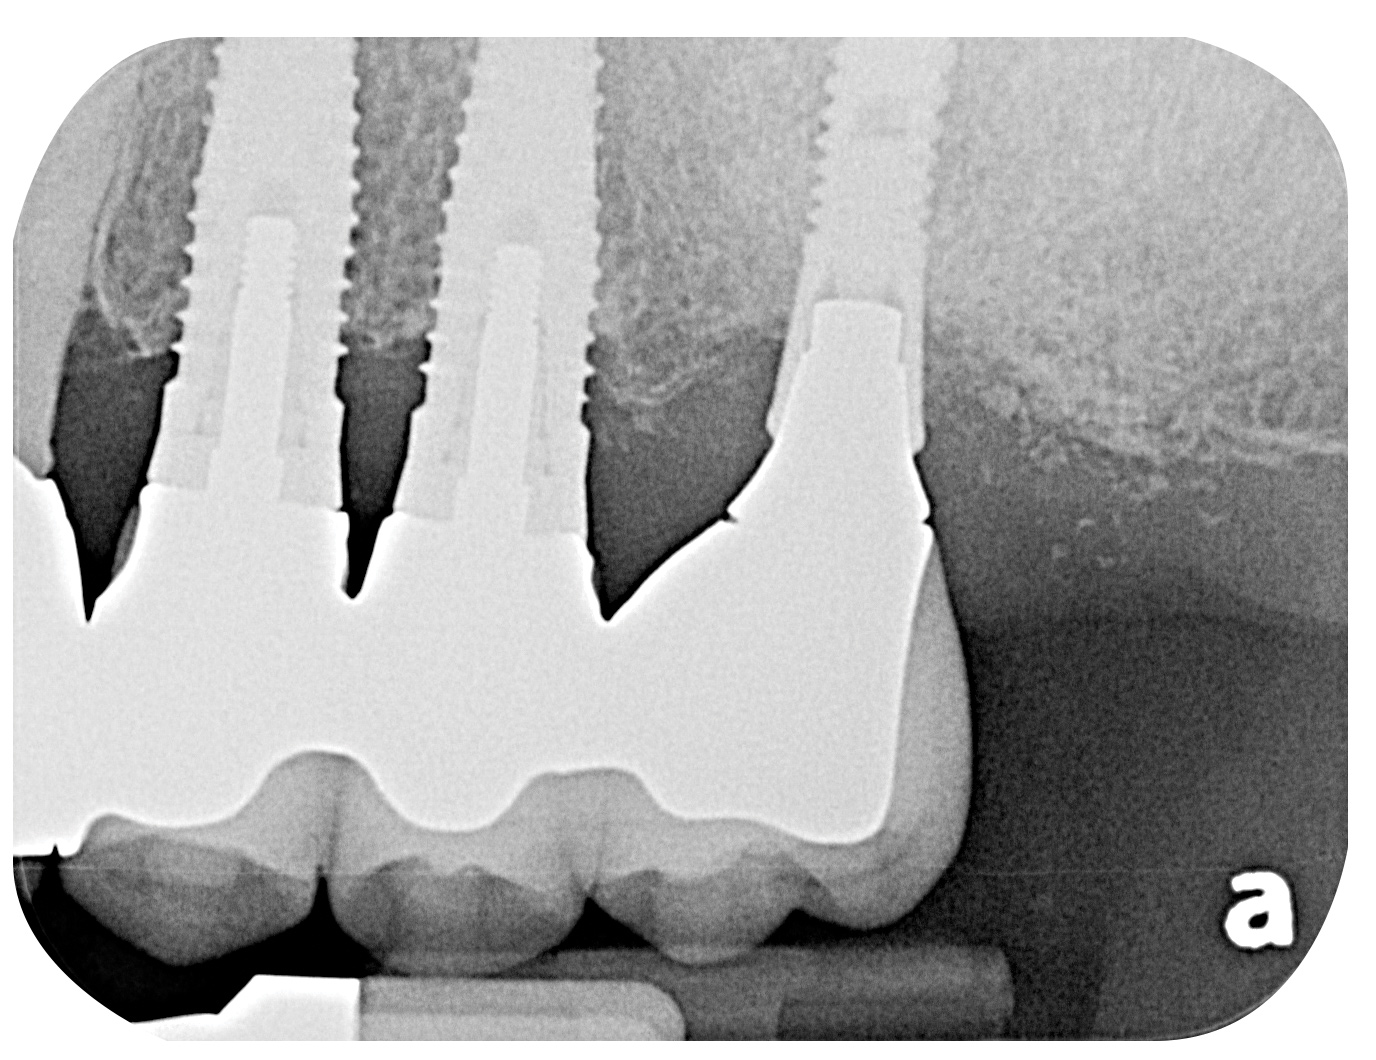

Fig 7. Radiographic image of the area suggesting severe bone loss around the dental implants.

Figure 7